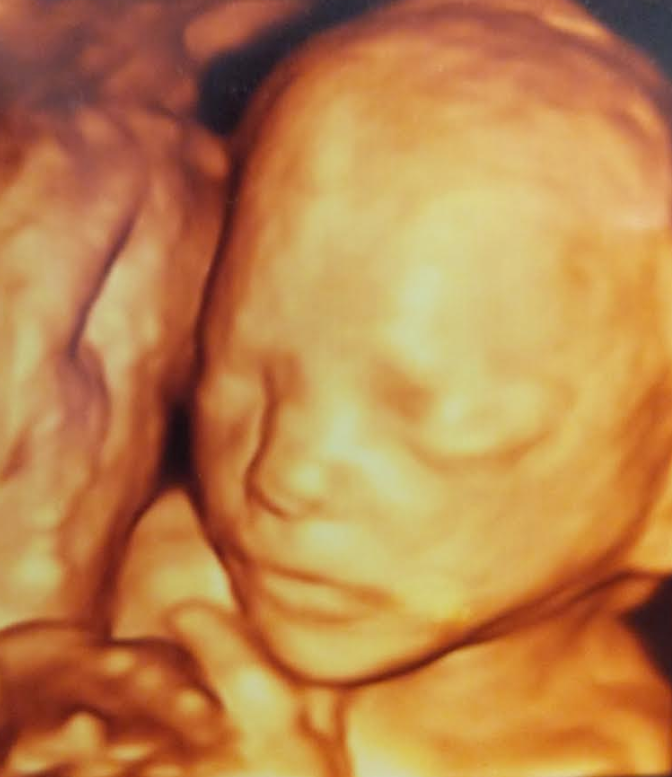

20-22 week Ultrasound . The detailed mid trimester scan is the single most important scan in pregnancy . This is the optimal time to detect fetal abnormality . Other issues such as placental site and growth will also be assessed . Generally, views of the baby are excellent and this scan is enjoyed enormously by parents .